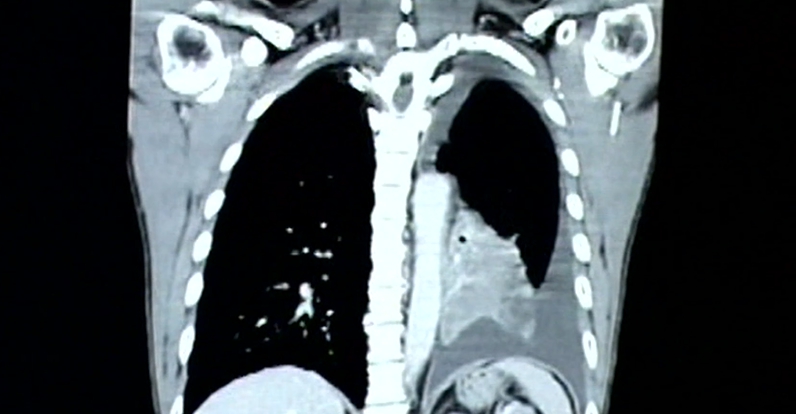

國內醫師也從臨床角度分析,男性生活型態不健康,導致慢性病纏身,當遇到相同病毒侵襲時,肺部受到的損傷,肯定會比較嚴重,自然也會有比較大致死風險。